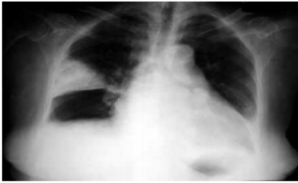

Paciente de 45 anos, dispneico. Feito apenas raio-x e ECG porque o laboratório está fechado. Qual é o provável diagnóstico, pelo raio-x e qual seria a alteração mais comum no ECG?